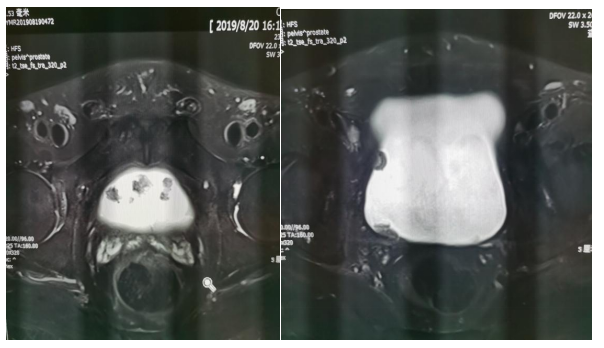

前列腺增生

膀胱癌